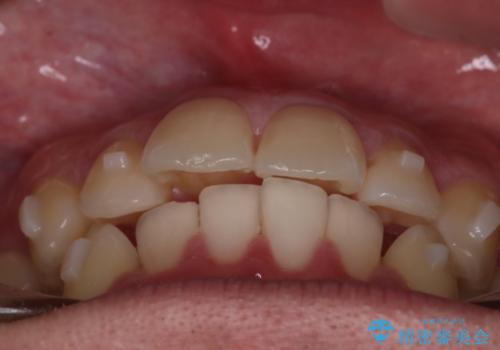

【インビザラインモニター】前歯が出ているのが気になる

- 上の前歯が出ているのが少し気になるとの事で来院されました。

インビザライン希望のため、IPR(歯と歯の間を削る処置)を行うことで、前歯の位置とがたつき整える治療計画を立てました。